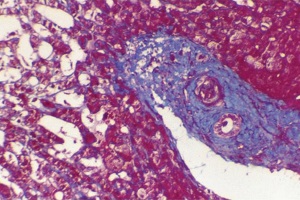

Цирроз печени – тяжелое хроническое заболевание, при котором функциональные клетки печени (гепатоциты) постепенно замещаются соединительной тканью, что приводит к уменьшению их общего количества.

К сожалению, в последнее время в гастроэнтерологической практике достаточно часто встречаются пациенты с фиброзом и циррозом печени.

Нецирротический фиброз печени (первичный гепатопортальный склероз) известен также под названиями идиопатическая портальная гипертензия, или нецирротический портальный фиброз.